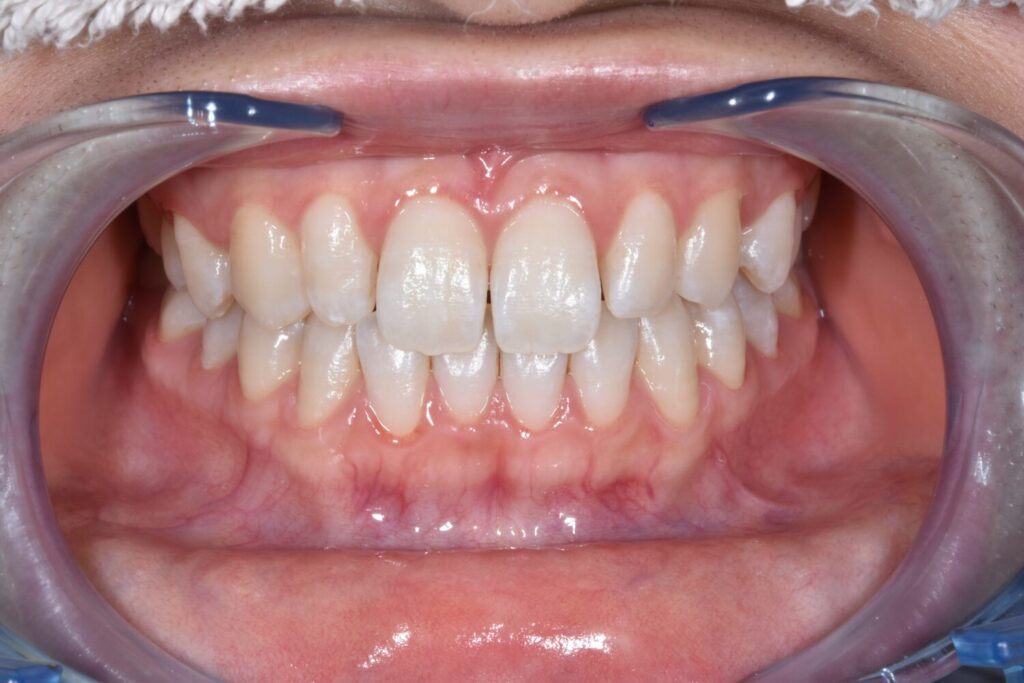

術後

リフレッシュケア+オプション(二次研磨:リナメルトリートメント)

¥9900+¥1100(オプション)

毎月定期的な検診・クリーニングに来てくださっている10代の患者様

保険内のクリーニングでは落としきれない着色汚れをリフレッシュケアで改善されました。